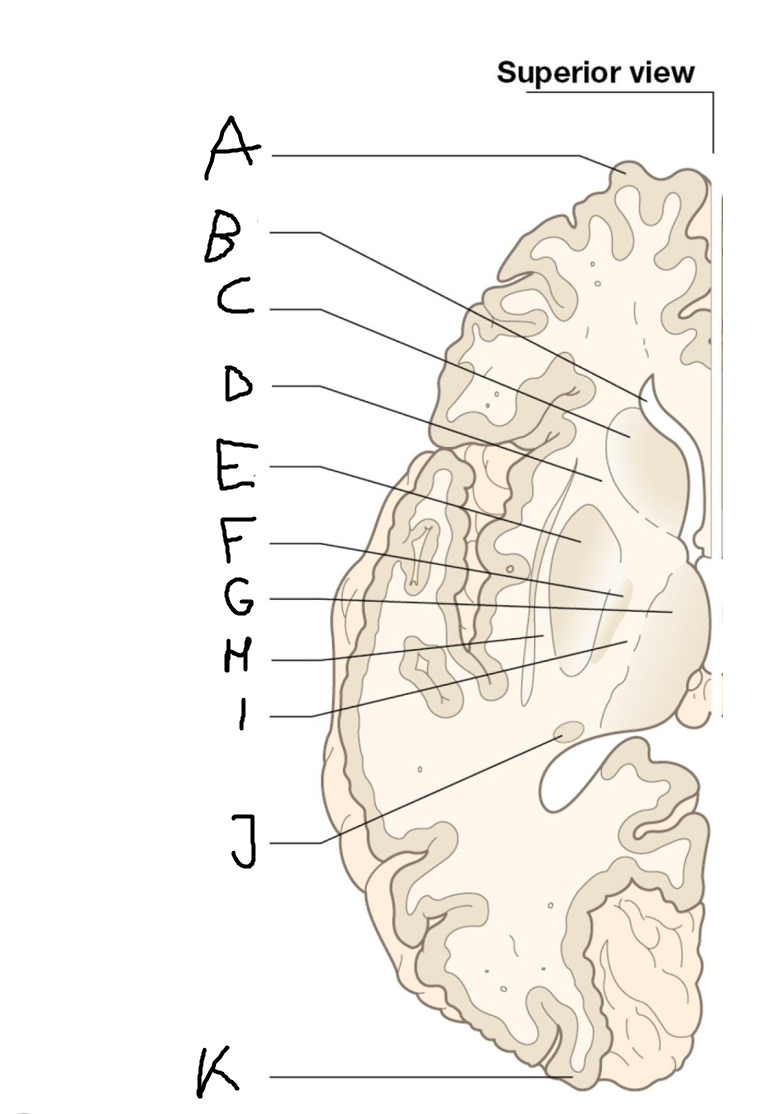

internal capsule (posterior limb)

B

anterior horn of lateral ventricle

C

head of caudate nucleus

D

internal capsule (anterior limb)

E

putamen

F

globus pallidus

G

Thalamus

H

External capsule

I

internal capsule (posterior limb)

J

tail of caudate nucleus